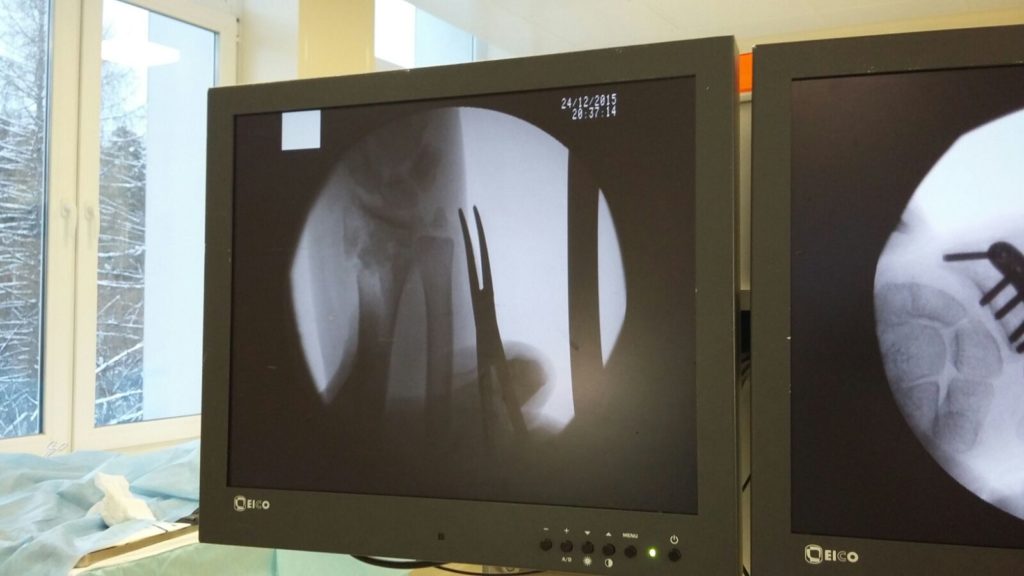

Операция - открытая репозиция, остеосинтез лучевой кости пластиной с костной ксенопластикой материалом "Остеоматрикс". На контрольных снимках в три месяца имеется консолидация перелома, миграции фиксатора нет, имеется остеоинтеграция ксенопластического материала.

Отдаленные результаты через 3 (три) месяца: